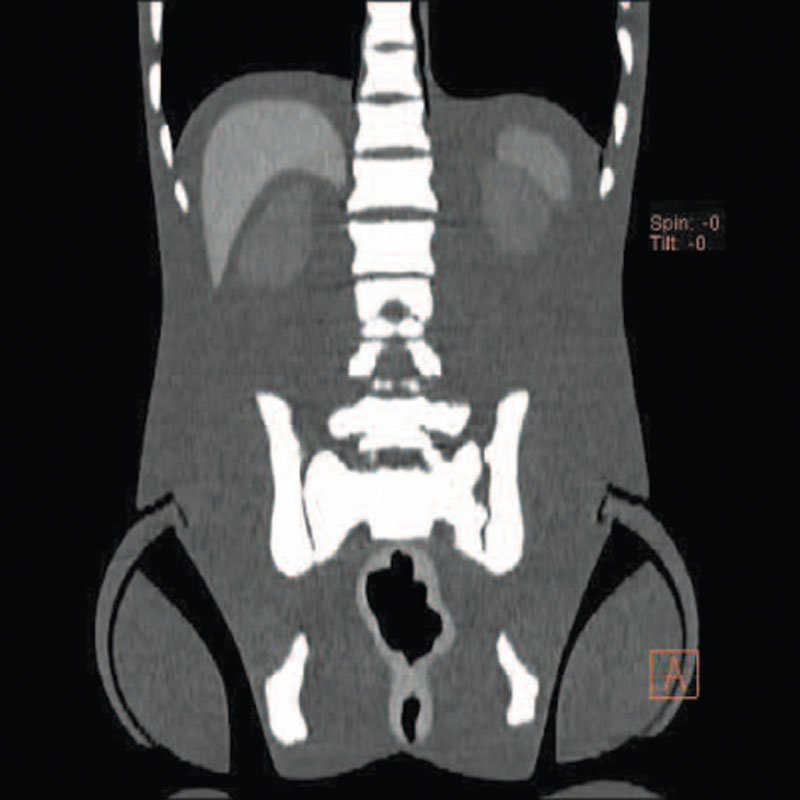

Ein einzigartiges Ganzkörperphantom für CT bietet eine Vielzahl von Ausbildungs- und Forschungsmöglichkeiten. Das Phantom kann auch für normales Röntgen benutzt werden und gibt lebensnahe Bilder. Es benden sich keine Metallteile oder Flüssigkeiten im Phantom. Die wichtigen Gelenke haben eine menschenähnliche Beweglichkeit und erlauben vielfältige Positionen für die Übung. Das Phantom kann in 10 Teile zerlegt werden. Die verbesserten Schultergelenke erlauben es, die Arme nach oben zu bewegen. Die künstlichen Organe sind anatomisch korrekt und haben entsprechende HU-Zahlen.

- Beckenknochen

- Aorta

- Vena Cava

- Harnleiter

- Harnblase

- Prostata

- Rektum

- Colon sigmoideum

Radiologische Absorption und Hounsfield-Nummer ähnlich dem menschlichen Körper.